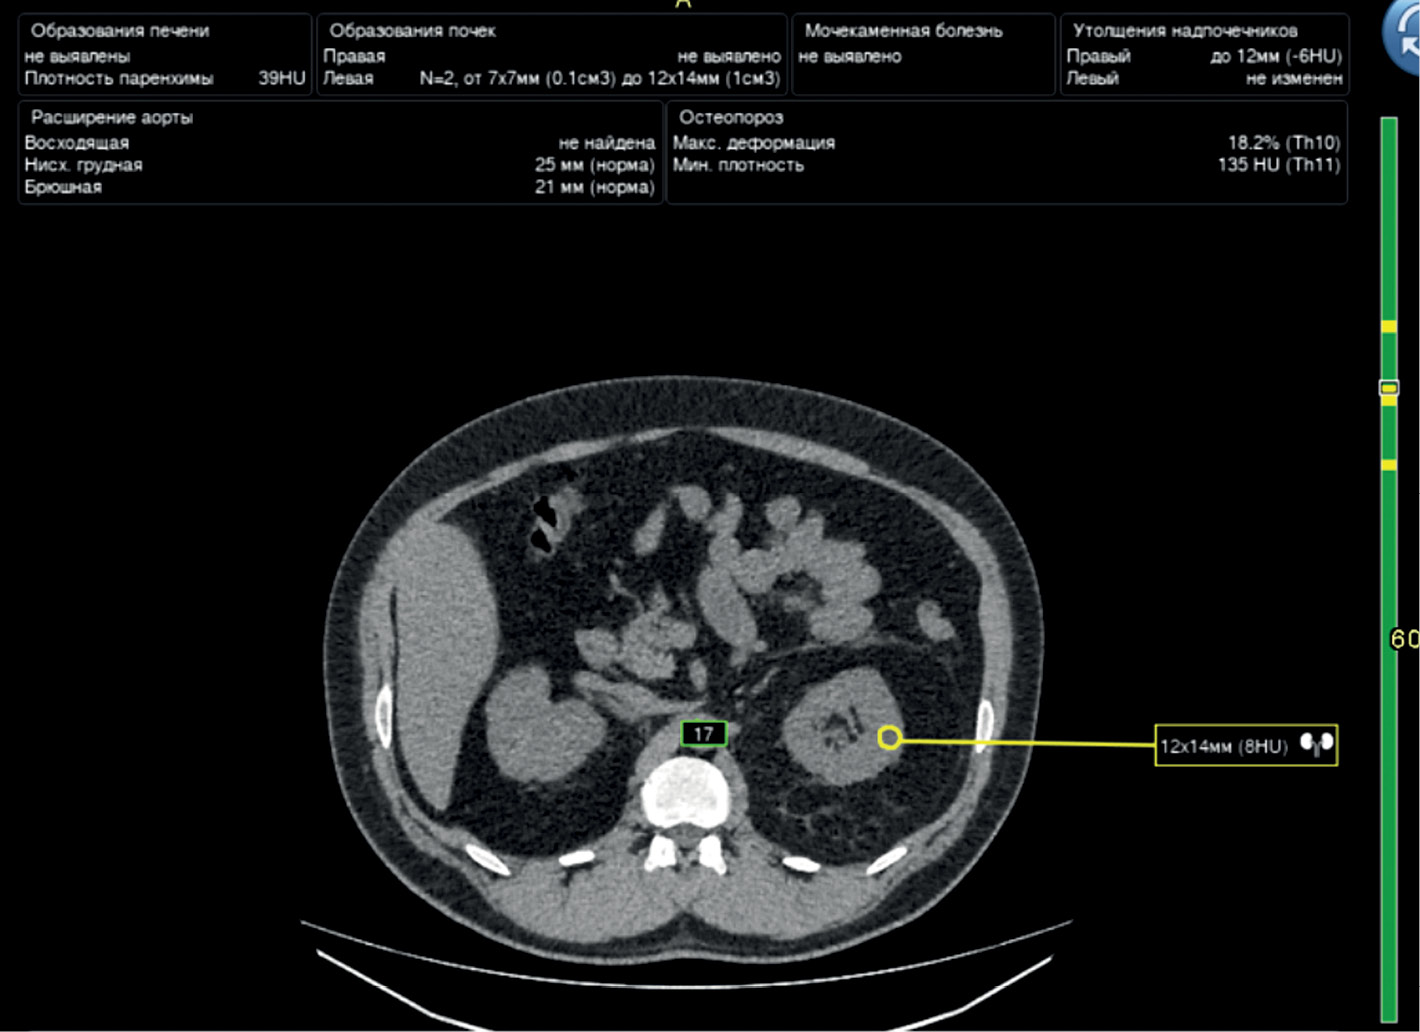

Other architectures (e.g., EffectiveNet) also demonstrate a high Dice coefficient for the segmentation of the kidneys and kidney neoplasms (up to 0.95) [27, 28]. An example of kidney neoplasm segmentation is presented in Fig. 3.

Fig. 3. An example of right kidney neoplasm segmentation.

Both classic machine-learning algorithms and deep-learning algorithms are used for the classification of kidney neoplasms [24, 26, 29–31]. Swin transformers architectures have the greatest accuracy (99.3%) [29].

When data are limited, classic machine-learning algorithms and feedforward architectures prove effective [26]. Similarly to the segmentation of the kidneys and kidney neoplasms, the classification performance of voxel-based architectures is noninferior to that of pixel-based architectures [31].